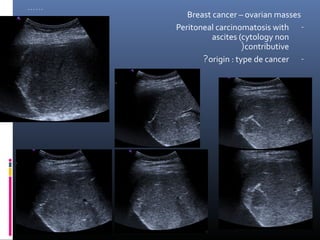

Breast cancer – ovarian masses

Peritoneal carcinomatosis with -

ascites (cytology non

(contributive

?origin : type de cancer -

…… Breast cancer – ovarian masses Peritoneal carcinomatosis with - ascites (cytology non (contributive ?origin : type de cancer -